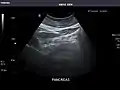

Kidneys: Right and left kidneys measure 11.5 cm and 12 cm in length respectively. No hydronephrosis. Small left lower pole kidney cyst.

Left kidney